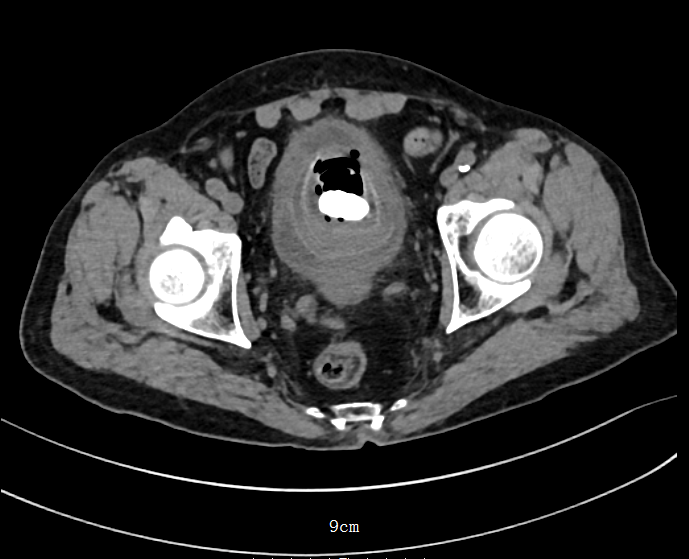

經(jīng)泌尿外科詳細(xì)檢查

醫(yī)生發(fā)現(xiàn)患者

前列腺體積增大至118立方厘米

而正常成年男性的前列腺體積

約為12立方厘米

同時,膀胱內(nèi)存在一枚巨大結(jié)石

直徑達(dá)5.8×5.1厘米

更令人震驚的是

影像學(xué)檢查顯示

這枚結(jié)石內(nèi)部含有氣體成分

即臨床上極為罕見的“含氣結(jié)石”